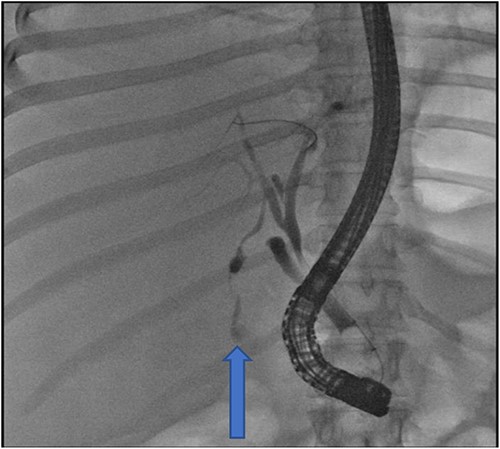

The following day, percutaneous drainage of the biloma was done through a pigtail catheter inserted through sub phrenic space access (Fig. 3). Subsequently after 6 days, drainage amount of the biloma markedly decreased and catheter was removed on the seventh day after insertion. The patient had marked symptom improvement afterwards, and control abdominal US was normal.

Insertion of percutaneous catheter drainage for drainage of biloma.